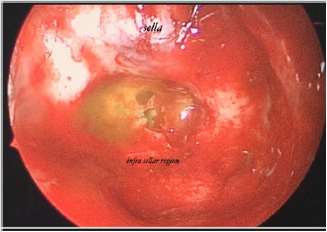

Figure 2: (a) intraoperative endoscopic view show csf leakage from clivus defect just inferior to sella.

(b) basilar artery in prepontine cistern behind the defect

A 57-year-old man referred for clear watery discharge from the right nostril of no obvious cause. He suffered from intermittent rhinorrhea starting 6 months prior to arrival. He reported recent history of bacterial meningitis one month ago, which was treated successfully at an outside hospital. On admission, he had no focal neurological deficits. Nasal fluid tested positive for beta 2 transferrin. Brain MRI revealed that the right sphenoid sinus was filled with CSF (Figure 4). CT cisternography showed that the contrast material passed from the prepontine cistern into the sphenoid sinus through this bone defect in the clivus (Figure 4). After intrathecal administration of 0.25mL of 10% fluorescein with 10 mL of cerebrospinal fluid the patient underwent endoscopic trans nasal approach. After stripping the mucosa from posterior wall of sphenoid sinus, CSF leak was observed in the upper region of clivus just below the sella at the midline (Figure 5). The defect was closed by abdominal fat and reinforced by fasciculata and naso septal flap. At the During 30-month follow-up appointment, no signs of recurrence were found. In both above reviewed cases, a lumbar drain was not placed pre or postoperatively.